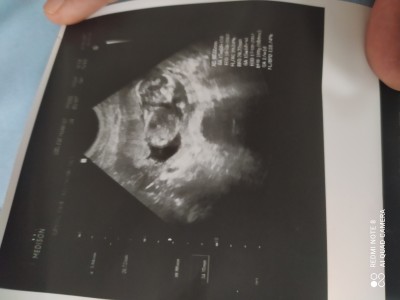

Cinsiyet tahmininde bulunabilirmisiniz

Cinsiyet tahmininde bulunabilirmisiniz.

Gebelik haftası

15+0

Resim net degıl orda bebek mı var

Evet 15 haftalk